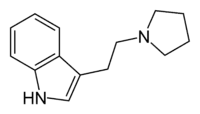

| Pyr-T | artificial | H | (CH2)4 | 3-[2-(Pyrrolidin-1-yl)ethyl]-1H-indole | 14008-96-9 | |